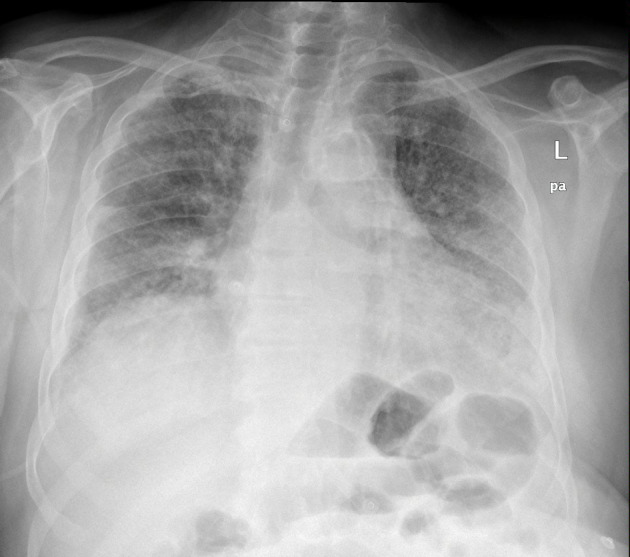

Immune checkpoint inhibitors like pembrolizumab represent a modern approach to the management of various malignancies, including non-small cell lung cancer. The therapeutic activity of immunotherapy is exerted by the activation of immune cells against the tumor cells. However, systemic activation of the immune system can lead to the development of autoimmune complications known as immune-related adverse events. A combination of rare immune-related adverse events is occasionally observed simultaneously in the same patient. We present the case of a 66-year-old male with squamous non-small cell lung carcinoma who presented to the emergency department with dyspnea and respiratory failure. Imaging findings were consistent with pulmonary embolism and nonspecific interstitial pneumonitis. One month before this event, he was diagnosed with bullous pemphigoid following 21 cycles of treatment with pembrolizumab. The radiological findings, the lack of response to antibiotics, the negative microbiological workup, and the excellent response to corticosteroids established the diagnosis of pembrolizumab-induced pneumonitis. The combination of bullous pemphigoid and pneumonitis secondary to pembrolizumab is rare; only a few case reports exist in the literature. Hence, this case highlights the possibility of multiple immune-related adverse events in the same patient. The exclusion of infectious diseases and other immunologic disorders with a similar clinical presentation is necessary to make the final diagnosis of immune-related adverse events and start the appropriate treatment. Serology, histopathology, and direct immunofluorescence aid to the diagnosis of immune-related bullous pemphigoid; the differential diagnosis includes other pemphigoid or lichenoid diseases, Stevens-Johnson syndrome/toxic epidermal necrolysis, and drug reaction with eosinophilia and systemic symptoms. Imaging, microbiological testing, and bronchoscopy (if possible) confirm the diagnosis of immune-related pneumonitis, which should be differentiated from acute coronary syndrome, cardiogenic pulmonary edema, pulmonary embolism, tumor progression, and lower respiratory tract infections (especially Pneumocystis jirovecii pneumonia in immunocompromised patients). An interdisciplinary approach is necessary for the management of these cases.